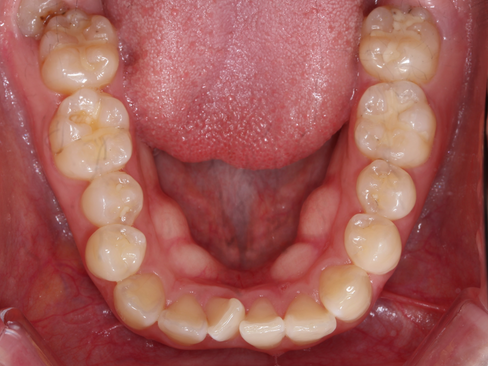

부산보철잘하는곳 초진 시 파노라마 및 위쪽 씹는면 구내사진과 X-ray 입니다.

위 사진은 초진 시 아랫니 씹는면 구내사진입니다.

교정을 진행하지 않는 치아라면 위 정도의 초기우식은 정기검진하며 지켜볼 수는 있으나 교정장치를 붙이고 나면 안쪽에서 충치가 얼마나 진행되는지 등 정기검진을 하 수 없기에 레진으로 간단하게 치료를 하였습니다.